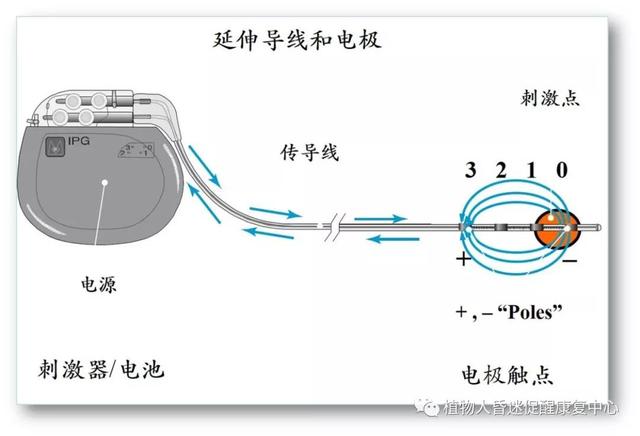

第二、脊髓电刺激(SCS): 作为神经调控治疗方式的一种,近来,对于脊髓电刺激(spinal cord stimulation, SCS)治疗意识障碍的关注逐渐升温。脊髓电刺激(SCS)通过手术放置刺激电极在颈髓C2-C4水平硬膜外正中部,电刺激通过上行性网状结构激活系统及丘脑下部激活系统传达到大脑皮层。有报告认为SCS可以调节局部脑血流量,从而引发作为意识相关神经环路的功能变化。目前较为明确的看法是,SCS可调节增加脑血流量,对于缺血性脑病有益。截至目前,发表的文献和数据共通过SCS治疗了308例PVS患者,51.6%有临床改进。

图5:脊髓电刺激示意图。